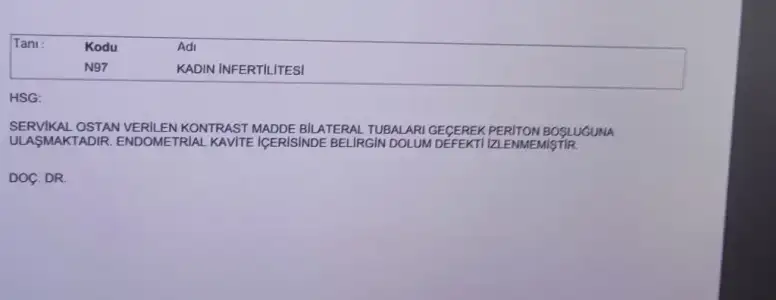

Dün anestezili hsg çektirdim, bugün de radyolojiden CD mi alıp doktorla görüştüm. Sağolun kağıda çizerek bilgisayarda göstererek anlattı. 3 yıllık evliyim 9 aydır deniyoruz. Rahim ağzım dar ve tıkalıymış meğer. Doktor önce görüntüde doğuştan Rahim küçük sanmış sonra tıkanıklığı giderince öyle olmadığını görmüş. Tüylerim açık. Tam istediğim görüntüyü elde edemedim ama tecrübeme dayanarak yorumlarsam şu an bi sorun yok gibi görünüyor. 2 3 ay içinde hamile kalamazsan tekrar gel bu defa kamera ile girip hem bakarız hem tekrar hsg çekeriz dedi. Hsg den sonra hamile kalan var mı aranızda? Nedense bi içim rahat değil.

Dün anestezili hsg çektirdim, bugün de radyolojiden CD mi alıp doktorla görüştüm. Sağolun kağıda çizerek bilgisayarda göstererek anlattı. 3 yıllık evliyim 9 aydır deniyoruz. Rahim ağzım dar ve tıkalıymış meğer. Doktor önce görüntüde doğuştan Rahim küçük sanmış sonra tıkanıklığı giderince öyle olmadığını görmüş. Tüylerim açık. Tam istediğim görüntüyü elde edemedim ama tecrübeme dayanarak yorumlarsam şu an bi sorun yok gibi görünüyor. 2 3 ay içinde hamile kalamazsan tekrar gel bu defa kamera ile girip hem bakarız hem tekrar hsg çekeriz dedi. Hsg den sonra hamile kalan var mı aranızda? Nedense bi içim rahat değil.